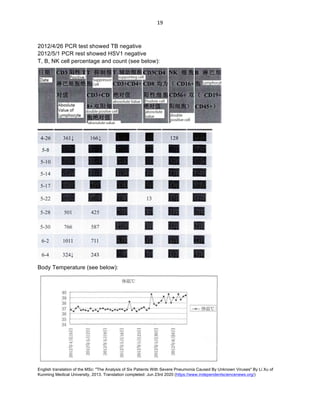

2012/4/26 PCR test showed TB negative

2012/5/1 PCR rest showed HSV1 negative

T, B, NK cell percentage and count (see below):

Body Temperature (see below):